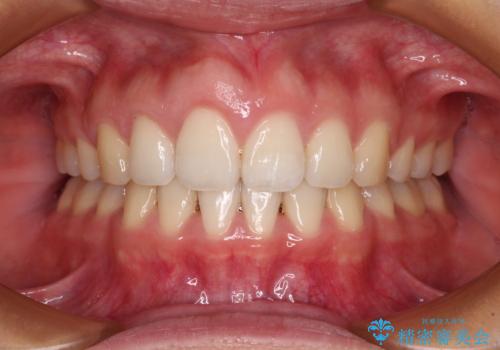

ワイヤー矯正と比較すると、八重歯が後方に傾斜した仕上がりとなりましたが、患者様ご希望のインビザラインにて十分な歯列を達成することができました。